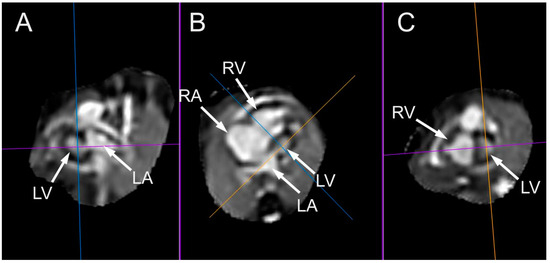

- Rubert, N.C.; Jategaonkar, G.; Plasencia, J.D.; Lindblade, C.L.; Bardo, D.M.E.; Goncalves, L.F. Four-dimensional fetal cardiac imaging in a cohort of fetuses with suspected congenital heart disease. Pediatr. Radiol. 2023, 53, 198–209. [Google Scholar] [CrossRef] [PubMed]